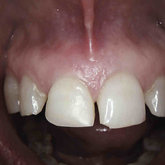

He received his Diploma in Implantology in 2016 from the University of Pretoria, which he passed with Distinction. He is also a member of the International Team for Implantology (ITI), which is based in Switzerland and offers members access to the latest research and cutting-edge techniques.

Porcelain crowns and restorations made in one appointment.

We make it a priority to incorporate the latest in dental technology in everything we do at our practice. ...